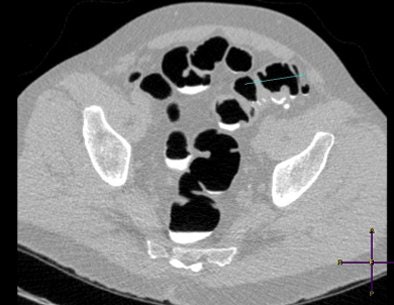

| A colon lumen filled with tagged feces -- a typical image with Telebrix preparation. Image courtesy of Dr. Marjolein Liedenbaum. |